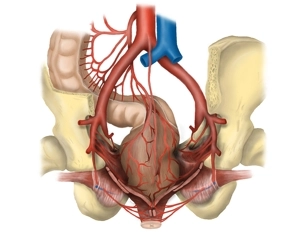

• Terço proximal do reto suprido pela artéria retal superior dividindo-se posteriormente em dois ramos terminais; terço médio pela artéria retal média (pareada, cada uma originando-se da artéria ilíaca interna); e o terço distal pela artéria retal inferior (pareada, cada uma originando-se da artéria ilíaca interna). As artérias retais médias cursam nos chamados ligamentos laterais do reto e são divididas na excisão mesorretal total.

• Sangue venoso do hemicólon esquerdo flui via veias de mesmo nome para a área drenada pela veia porta.

• Drenagem venosa do terço proximal e médio via veia mesentérica inferior (drenando para a veia porta), enquanto o sangue venoso do terço distal retorna via área drenada pela veia cava inferior.